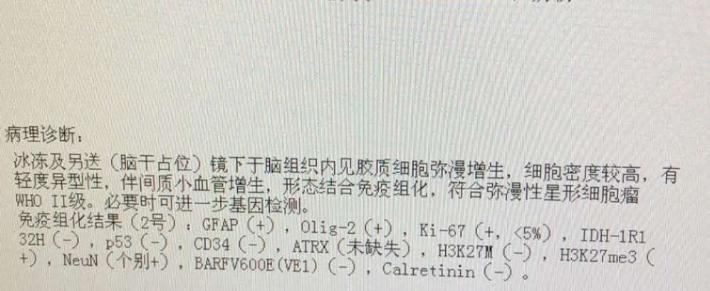

病理星形细胞瘤2级